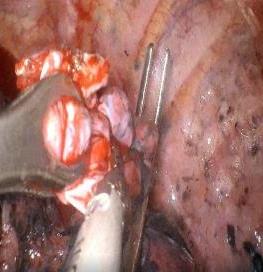

• 吲哚菁绿荧光引导腹腔镜胆囊切除术治疗急性胆囊炎的临床疗效及其术后并发症相关因素分析

摘要:目的 探究吲哚菁绿(ICG)荧光引导腹腔镜胆囊切除术(LC)治疗急性胆囊炎的临床疗效,并分析发生术后并发症的相关因素。方法 回顾性分析2020年9月-2024年9月于该院行LC治疗的279例急性胆囊炎患者的临床资料。其中,行ICG荧光引导LC的179例患者为荧光组[按术前注射剂量和时间分为:A组(47例,15 min,2.5 mg)、B组(45例,30 min,2.5 mg)、C组(48例,30 min,5.0 mg)和D组(39例,60 min 5.0 mg),观察4组术中荧光显影情况],同期行常规LC的100例患者为白光组。比较荧光组和白光组患者围术期指标、肝功能及术后3个月并发症的发生情况;采用多因素Logistic回归模型,分析急性胆囊炎患者行ICG荧光引导LC术后发生并发症的危险因素,并构建决策树模型。结果 A组肝脏荧光强度高于B组、C组和D组,差异有统计学意义(P < 0.05);B组的胆囊管与肝脏荧光强度对比值高于A组、C组和D组,差异有统计学意义(P < 0.05)。荧光组的完全解剖胆囊三角时间、手术时间和术后住院时间明显短于白光组,术中出血量少于白光组,差异均有统计学意义(P < 0.05)。多因素Logistic回归分析显示,体重指数(BMI) ≥ 25 kg/m2OR^ = 3.534,95%CI:1.057~11.811)、发作至手术时间 ≥ 72 h(OR^ = 3.208,95%CI:1.227~8.390)、有三角解剖变异(OR^ = 2.870,95%CI:1.085~7.590)、胆囊壁厚度 ≥ 5 mm(OR^ = 2.957,95%CI:1.147~7.625)和美国麻醉医师协会(ASA)分级为Ⅲ级~Ⅳ级(OR^ = 3.179,95%CI:1.245~8.118),均为急性胆囊炎患者行ICG荧光引导LC术后发生并发症的独立危险因素(P < 0.05),医师熟练程度 ≥ 5年(OR^ = 0.280,95%CI:0.081~0.970)是急性胆囊炎患者行ICG荧光引导LC术后发生并发症的保护因素(P < 0.05)。决策树模型显示,医师熟练程度是最重要的预测因子,模型的分类准确率为91.40%。结论 急性胆囊炎患者术前30 min注射2.5 mg的ICG,可获得最佳术中荧光显影。对于行LC治疗的急性胆囊炎患者,ICG荧光引导LC,安全有效,可缩短手术时间,减少出血,加快康复。BMI ≥ 25 kg/m2、发作至手术时间 ≥ 72 h、三角解剖变异、胆囊壁厚度 ≥ 5 mm和ASA分级为Ⅲ级~Ⅳ级,是急性胆囊炎患者行ICG荧光引导LC术后发生并发症的独立危险因素,医师熟练程度 ≥ 5年是保护因素,术前应充分评估,以降低术后发生并发症的风险。